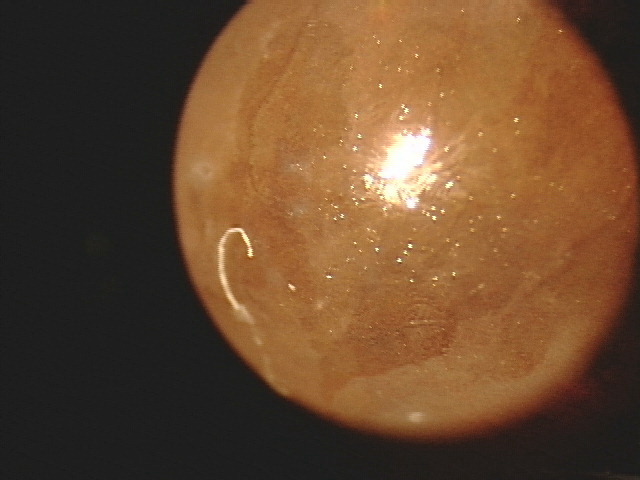

第1回目の写真は、、、進行してしまった「ドライアイ」です。

涙が少なくなることにより、目の表面の乾燥、どろっとした目ヤニ、目の充血、色素沈着(写真のような透明性が失われる)を起こす病気です。原因としては自己免疫疾患が一番多いです。